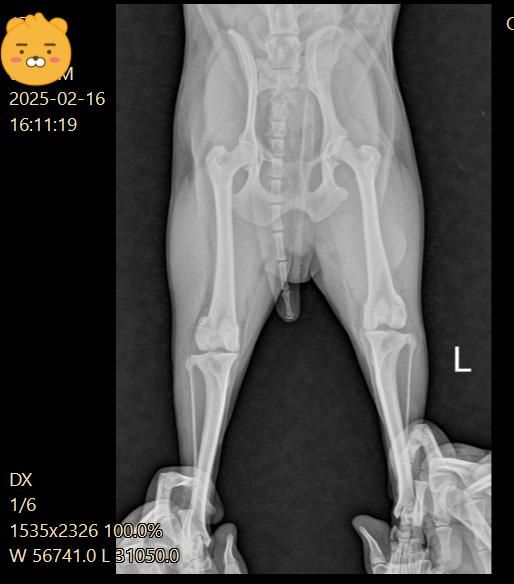

강아지 십자인대 파열로 볼 수 있나요? (엑스레이 첨부)

첫 진료 당시 십자인대 부분 파열이라고 했는데

5일후 진료는 십자인대는 애매하고 슬개골 2기로 수술 권유 받았어요

십자인대는 열어봐야 알 것 같다고 하셨고요

첫번째 진료는 십자인대 부분파열로 볼 수 있고

두번째 진료 엑스레이 상으로는 잘 안보이는것이 맞나요?

(첫번째 진료)

우측 관절낭이 좌측에 비해 종창 되어 관찰되고 경골 경사면 각도가 비교적 크게 관찰되어 십자인대에 손상이 있을 가능성이 있는 사진입니다. 이를 확인하기 위해서는 MRI 촬영이 필요하지만 현실적인 검사 방법은 아니라 추정일 뿐입니다. 하지만 방사선학적 관점에서 십자인대의 인장성 손상은 합리적인 추론입니다.